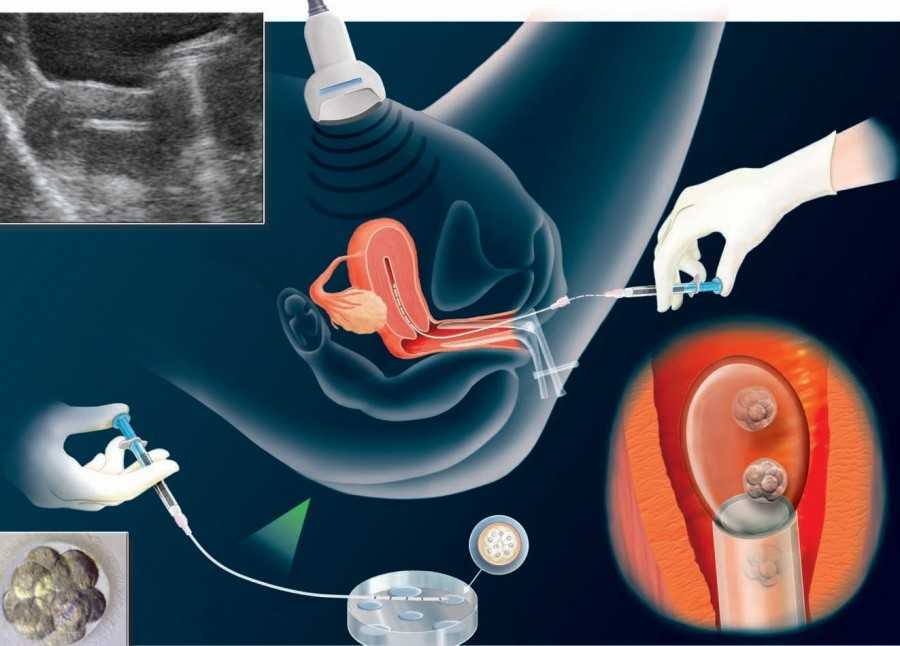

Также показано ультразвуковое исследование плода. Процедура УЗИ позволяет определить срок беременности, толщину плаценты, а также общее состояние яичников и пуповины.

На УЗИ плода на 9 неделе определяется толщина плаценты и общее состояние пуповины. При помощи допплера, будущая мама может отметить частоту сердечных сокращений малыша. Хотя многие внутренние органы уже достаточно развиты, это не всегда можно увидеть на УЗИ на 9 неделе.

На УЗИ на данном сроке обязательным является общая оценка состояния яичников.